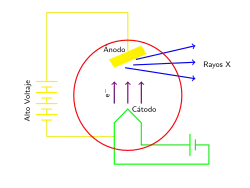

Para la producción de rayos X en laboratorios y hospitales se usan los tubos de rayos X, que pueden ser de dos clases: tubos con filamento o tubos con gas.

El tubo con filamento es un tubo de vidrio al vacío en el cual se encuentran dos electrodos en sus extremos. El cátodo es un filamento de tungsteno y el ánodo es un bloque de metal con una línea característica de emisión de la energía deseada. Los electrones generados en el cátodo son enfocados hacia un punto en el blanco (que por lo general posee una inclinación de 45°) y los rayos X son generados como producto de la colisión. El total de la radiación que se consigue equivale al 1% de la energía emitida; el resto son electrones y energía térmica, por lo cual el ánodo debe estar refrigerado para evitar el sobrecalentamiento de la estructura. A veces, el ánodo se monta sobre un motor rotatorio; al girar continuamente el calentamiento se reparte por toda la superficie del ánodo y se puede operar a mayor potencia. En este caso el dispositivo se conoce como «ánodo rotatorio».[2] El tubo de rayos X posee una ventana transparente a los rayos X, elaborada en berilio, aluminio o mica.

El tubo de rayos X está conformado por dos electrodos (cátodo y ánodo), una fuente de electrones (cátodo caliente) y un blanco. Los electrones se aceleran mediante una diferencia de potencial entre el cátodo y el ánodo. La radiación es producida justo en la zona de impacto de los electrones y se emite en todas direcciones.